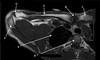

40

What is letter A?

HUMERAL HEAD

41

What is letter B?

ACROMION

42

What is letter C?

CLAVICLE

43

What is letter D?

STERNOCLAVICULAR JOINT

44

What is letter E?

STERNUM

45

What is letter F?

CORACOID PROCESS

46

TRICEPS MUSCLE

47

TRICEPS TENDON

48

FATTY TISSUE

49

OLECRANON

50

MEDIAL EPICONDYLE

51

ULNA

52

LATERAL EPICONDYLE

53

HUMERUS